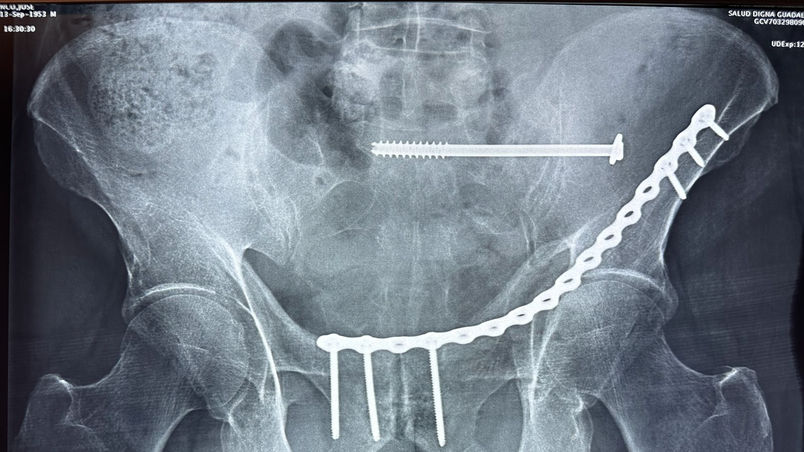

Fracturas y luxaciones.

Reducción y estabilización de fracturas y luxaciones.

Cirugía de urgencia en casos que lo requieren.